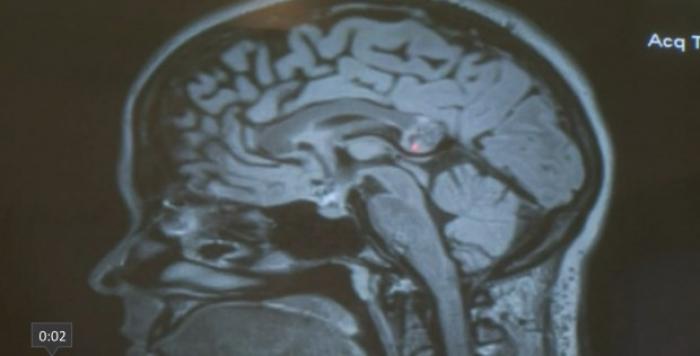

O tânără s-a trezit, peste noapte, cu dificultăți de înțelegere și ascultare. Pur și simplu, nu mai înțelegea ce se petrece în jurul ei. Când a ajuns la spital, doctorii au fost aproape siguri că se confruntă cu o tumoră cerebrală - adevărul, însă, era cu totul altul!